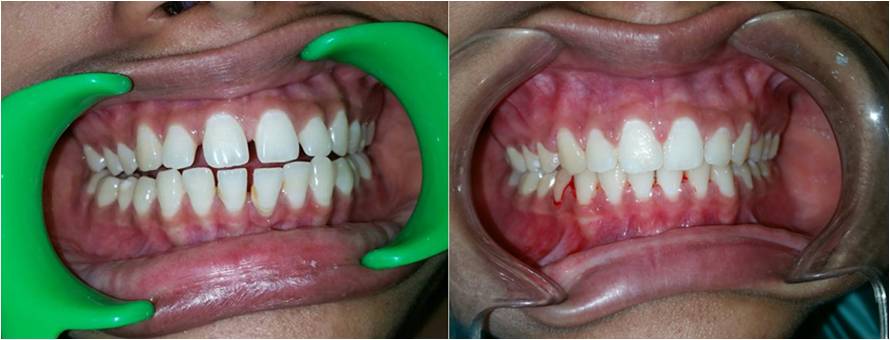

Cosmetic Dentistry